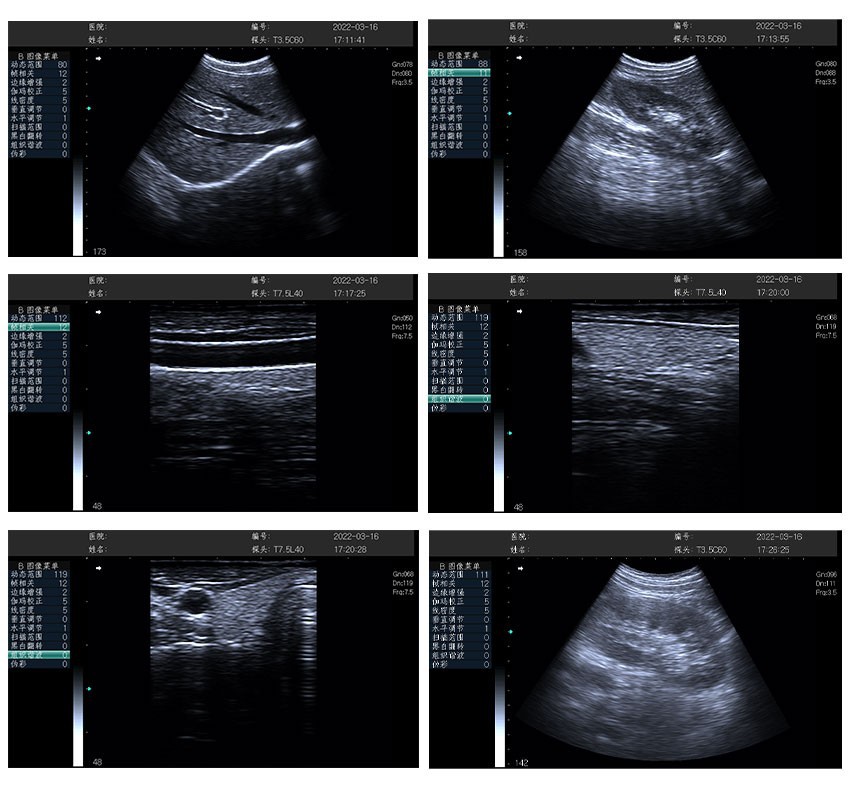

CS131 hágæða svart-hvíta hjartaómskoðunarvélin er sérhæft, færanlegt greiningarkerfi sem er hannað til að skila einstökum skýrleika og áreiðanleika fyrir hjartamyndatöku. Með því að blanda saman fullri-stafrænni tækni, -notendavænni notkun og langvarandi-hreyfanleika, setur það sjóngerð hjartabyggingar og virknimat í forgang, en styður samhliða notkun á mörgum-sérgreinum. Tilvalið fyrir sjúkrahús, hjartastofur, farsíma læknateymi og neyðarstillingar, það jafnvægir saman háa-afköst og hagkvæmni-sem gerir læknum kleift að framkvæma nákvæmar hjartarannsóknir hvenær sem er og hvar sem er.

- Sveigjanlegar myndatökustillingar: Styður B, 2B, 4B, M og B/M stillingar-M ham og B/M hamur skara fram úr við að fylgjast með hjartahreyfingum (td lokuhreyfingum, sleglasamdrætti) fyrir kraftmikla virknigreiningu.

Hjartapróf:Mat á stærð hjartahólfs, sleglaveggþykkt, lokubyggingu og kraftmikla hreyfingu (styður undirstöðumat á hjartastarfsemi vegna hjartsláttartruflana, hjartavöðvakvilla eða eftirfylgni- eftir-hjartaaðgerð).